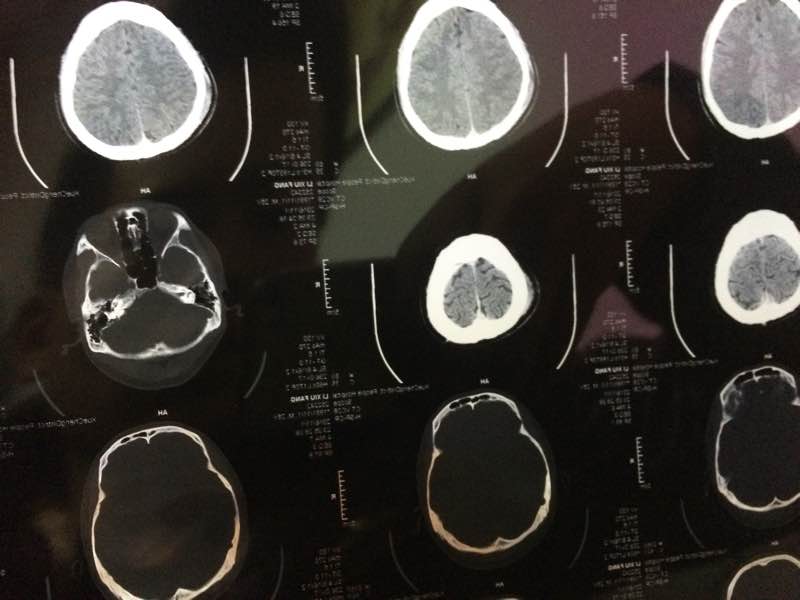

求大神帮忙看看,头还蒙蒙的